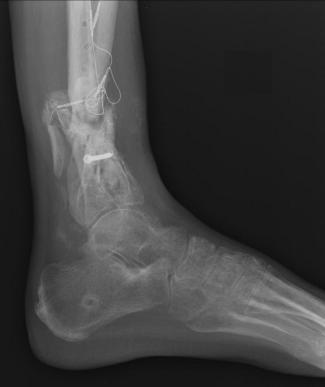

Pre-corrective surgery X-Rays of the damaged right & left legs / ankles

These x-rays were taken at Dr Armendariz’s office, just prior to performing any corrective surgery. As can be seen in these images,

there was no tibia bracing provided by Dr. Keller. Liam was released from Dr Keller’s care with instructions that full weight bearing could

be accomplished within 2 months of Keller’s last surgical procedure. The best example to examine is the second image (from the left) of the

top how. Notice how the bones that should be aligned with the tibia are in fact on the other side of the leg. The third image shows how badly

Liam’s left foot was twisted as a result of the pool placement of the external fixation. What is not obvious is that the screw at the bottom

of the plate on the right fibula missed being screwed into the plate.